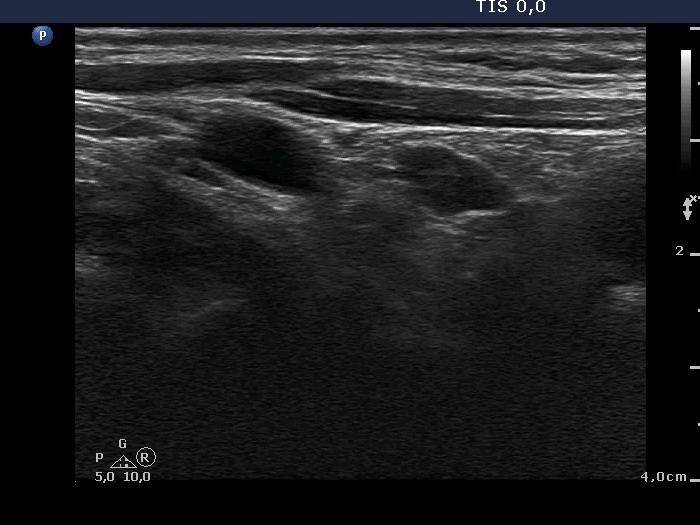

Ultrasound. Connective tissue replaced the thyroid parenchyma in both thyroid beds. There were tiny hypoechoic areas in the right thyroid bed. Two larger hypoechoic lesions were found, one in the isthmus and the other in the left thyroid bed. The latter presented vascularity.

Comment. The presentations of the hypoechoic lesion in all three sites were the same, they differed only in their size. Naturally, the two larger in the isthmus and in the left thyroid bed could cause and did cause concern. Especially that in the left lobe due to its intralesional vascularity. The larger lesions can correspond to small muscle fibers, remnant of the regenerative provess after the surgery but even damaged, non-viable thyroid tissue. Taking the thyroglobulin level into account, the risk of thyroid cancer is minimal but not zero.